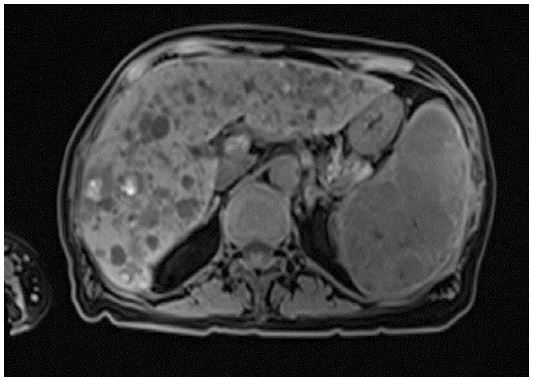

Magnetic resonance imaging of the liver was ordered for further delineation of lesions which revealed multiple liver cystic lesions, some with T1w hyperintense signal while others demonstrated internal filling defects (Figure 1). Differentials included polycystic liver disease or biliary hamartomas. Enhancing splenic lesions were also noted and differentials included hamartoma, lymphangioma, extramedullary haematopoiesis or angiosarcoma.

On an MR liver, the splenic lesions demonstrated heterogenous T1 hypointensity with and T2 hyperintense signal. The liver lesions were found to be cystic in nature, some with internal T1 hyperintense signal and in keeping with foci of haemorrhage. A PET CT demonstrated increased avidity of the splenic, liver and bone lesions.

Figure 4: Axial T1 weighted image demonstrating hyperintesnse foci within the liver lesions, in keeping with haemorrhagic foci.